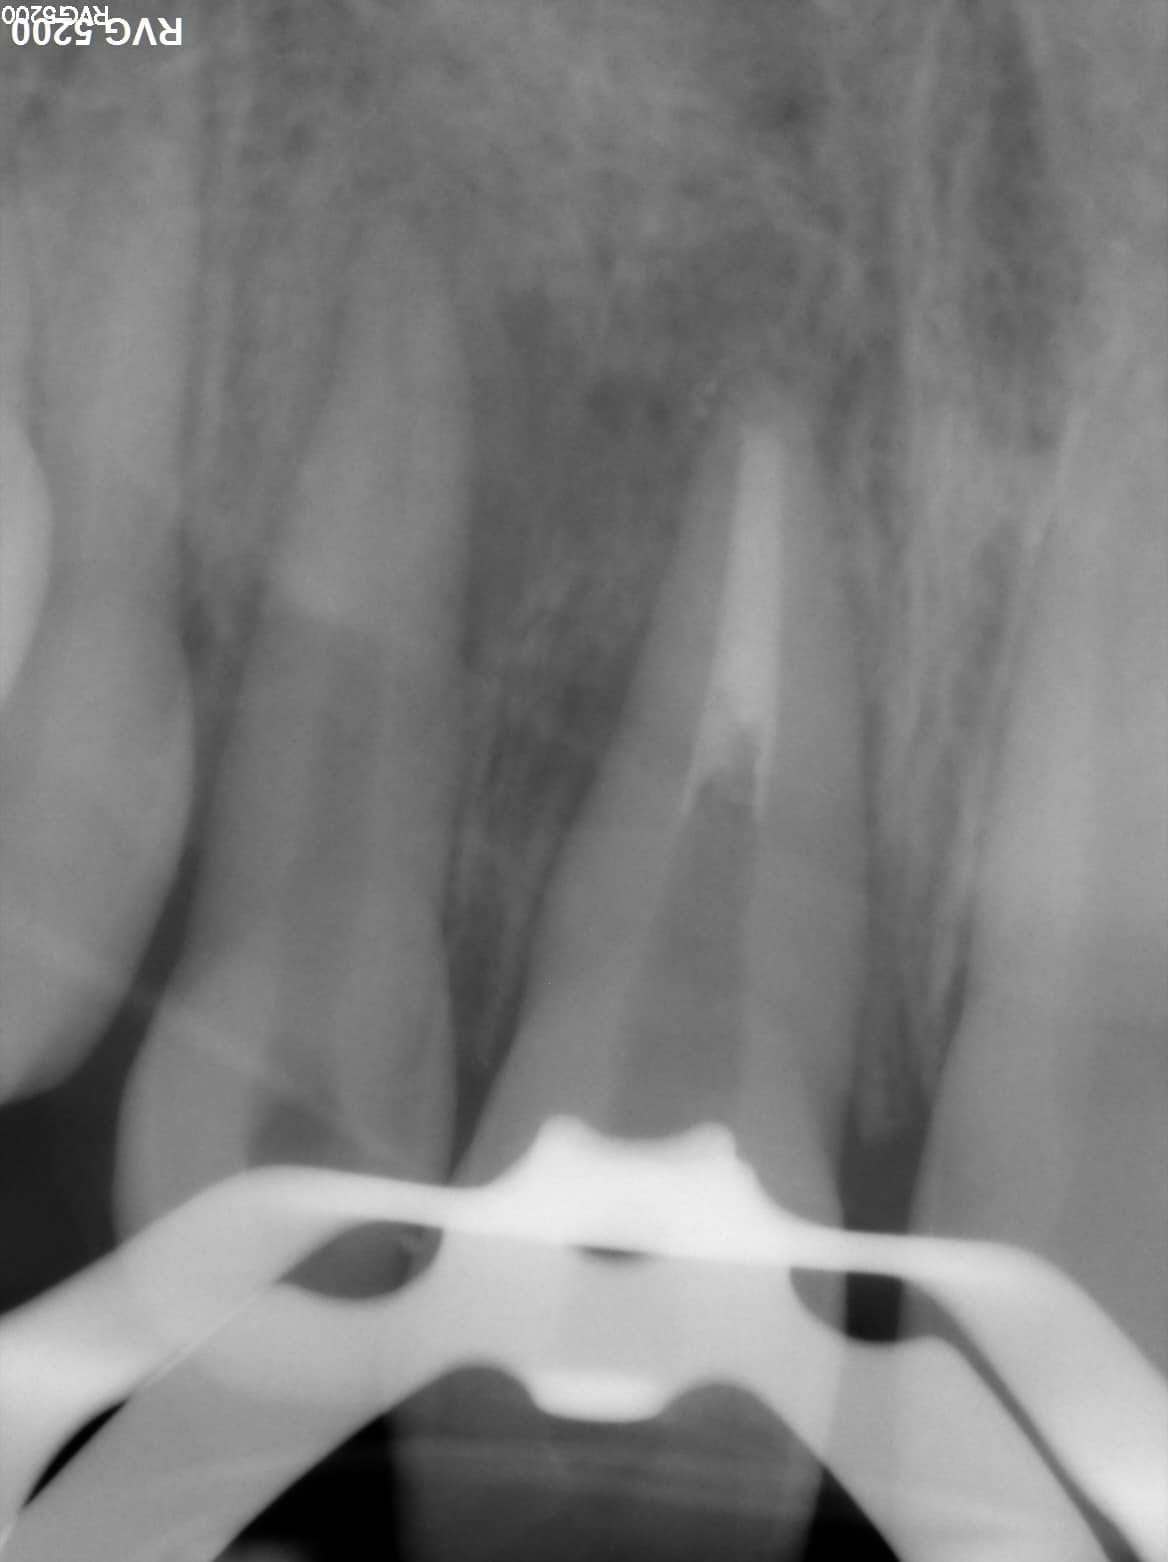

MTA plug radiograph